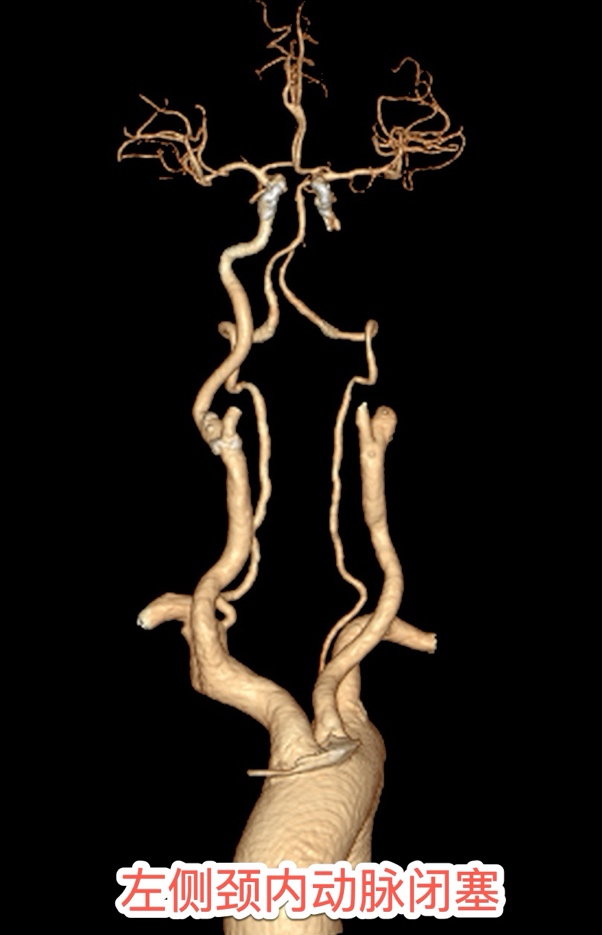

CTA锁定“元凶”:颈内动脉完全闭塞

在移动监护设备全程护航下,患者被直接推送至CT室。头颈部CTA检查显示左侧颈内动脉完全闭塞——这是给大脑半球供血的核心通道,每延迟1分钟就有190万个神经元死亡。头部CTP提示左侧大脑半球大面积“缺血半暗带”,这部分脑组织是可以被挽救的脑组织,恢复血流可以恢复正常功能的脑组织。情况十分危急,时间就是大脑,越早开通梗死面积越小,预后就越好。